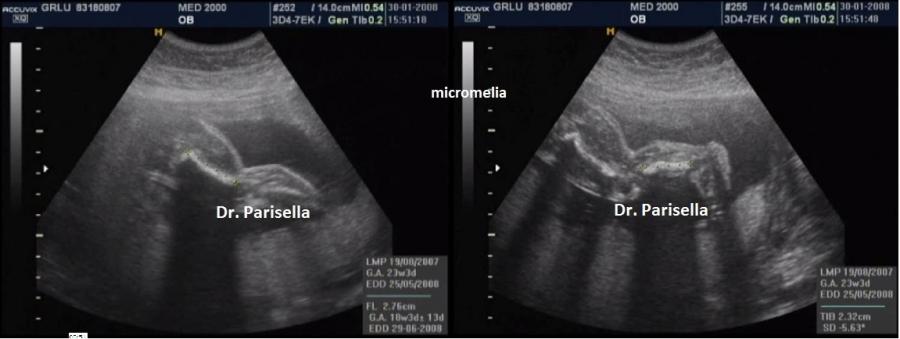

micromelia

La displasia boomerang รจ una sindrome estremamente rara caratterizzata da nanismo micromelico con arti ricurvi e rigidi, difetti di ossificazione, aplasia della fibula, aplasia del radio, facies caratteristica con radice del naso ampia ed ipoplasia delle narici e del setto nasale.

Il termine boomerang si riferisce alla particolare forma delle ossa lunghe delle gambe.